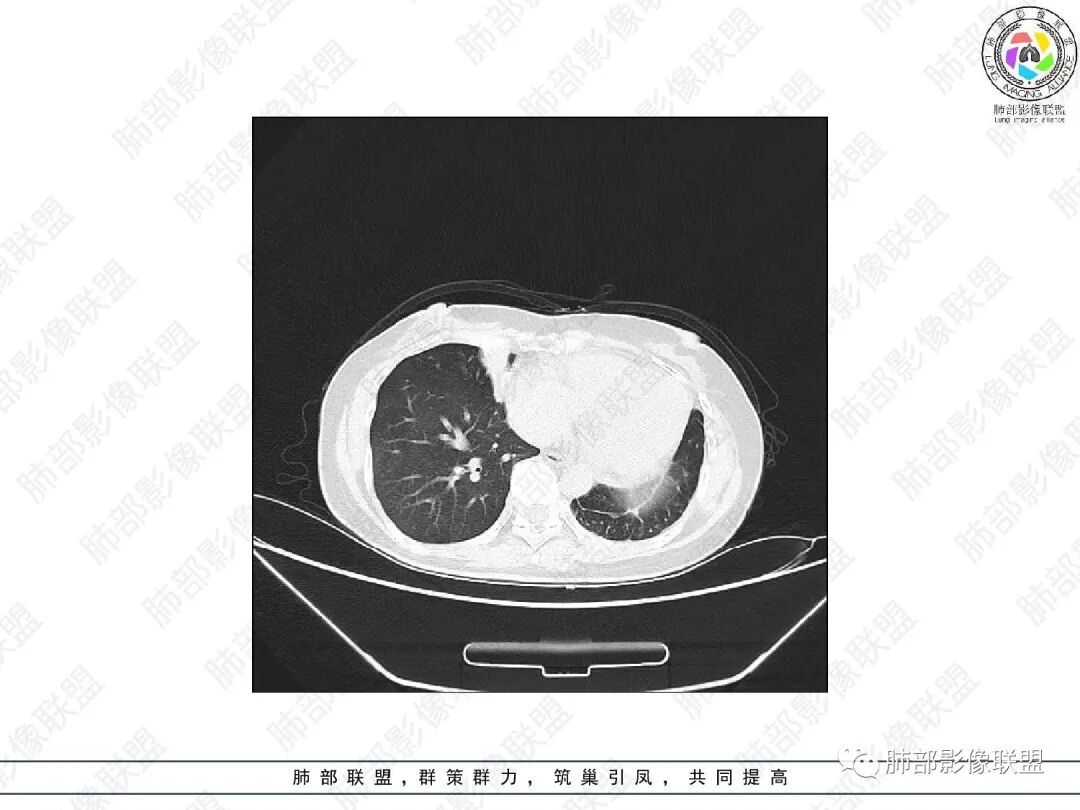

1.中年女性,主因“咳嗽、咳痰半年余”入院,既往史:8年前因左肺病在外院变行左肺叶切除术,诉术后抗结核治疗1年,具体病理等不详。实验室IGE显著增高。

2.胸部CT:右肺上叶及中叶不规则块状影,沿支气管走行方向指套样影,支气阻塞湖嵌塞,腔内可见高密度影。灶周可见磨玻璃,外围见结节影及树芽征。左肺体积缩小,见不规则条索影、胸膜增厚,纵隔牵拉左移。

3.综合分析:结合患者病史及胸部CT主要鉴别ABPA(右肺上叶不规则块影,指套样顺延支气管方向,抗结核治疗1年,肺部病灶仍明显)及继发性肺结核TB(右肺上叶不规则肿块,其可见高密影,边缘模糊,周围卫星灶、树芽征,沿支气管爬行)。

完善气管镜及病理、检验结果(IgE显著增高)等支持ABPA诊断。且给予激素及伊曲康唑治疗后复查胸部CT提示病灶较前吸收,所以诊断明确。